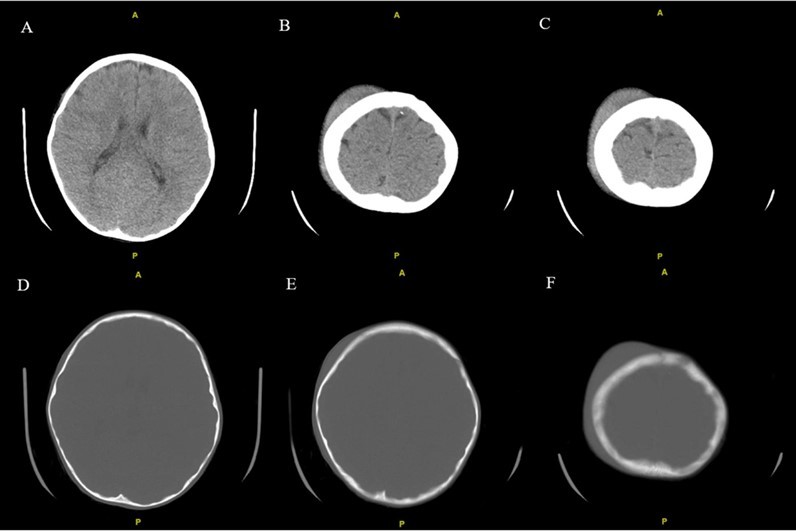

From a musculoskeletal standpoint, MRIs of the cervical, thoracic, and lumbar spine were within normal limits. The patient was started on scheduled acetaminophen for pain management. A CT of the head without contrast showed right high convexity scalp soft tissue swelling without acute intracranial abnormality (Figure 1A – 1F). A complete bone survey was negative for sources of trauma (Figure 2B – 2I) but did note calvarial soft tissue edema (Figure 2A). A head ultrasound confirmed the fluctuance on the patient’s skull to be a subgaleal hemorrhage (Figure 3A – 3C) of 9 mm thickness at its greatest.

Figure 1A - 1F.Noncontrast CT examination of the brain. Multiple axial images were obtained. Images listed from superior to inferior. Adjustment of the MA and/or KV was done according to the patient's size. Findings include right high convexity scalp soft tissue swelling without acute intracranial abnormality.

Noncontrast CT examination of the brain. Multiple axial images were obtained. Images listed from superior to inferior.  Adjustment of the MA and/or KV was done according to the patient's size. Findings include right high convexity scalp soft tissue swelling without acute intracranial abnormality.